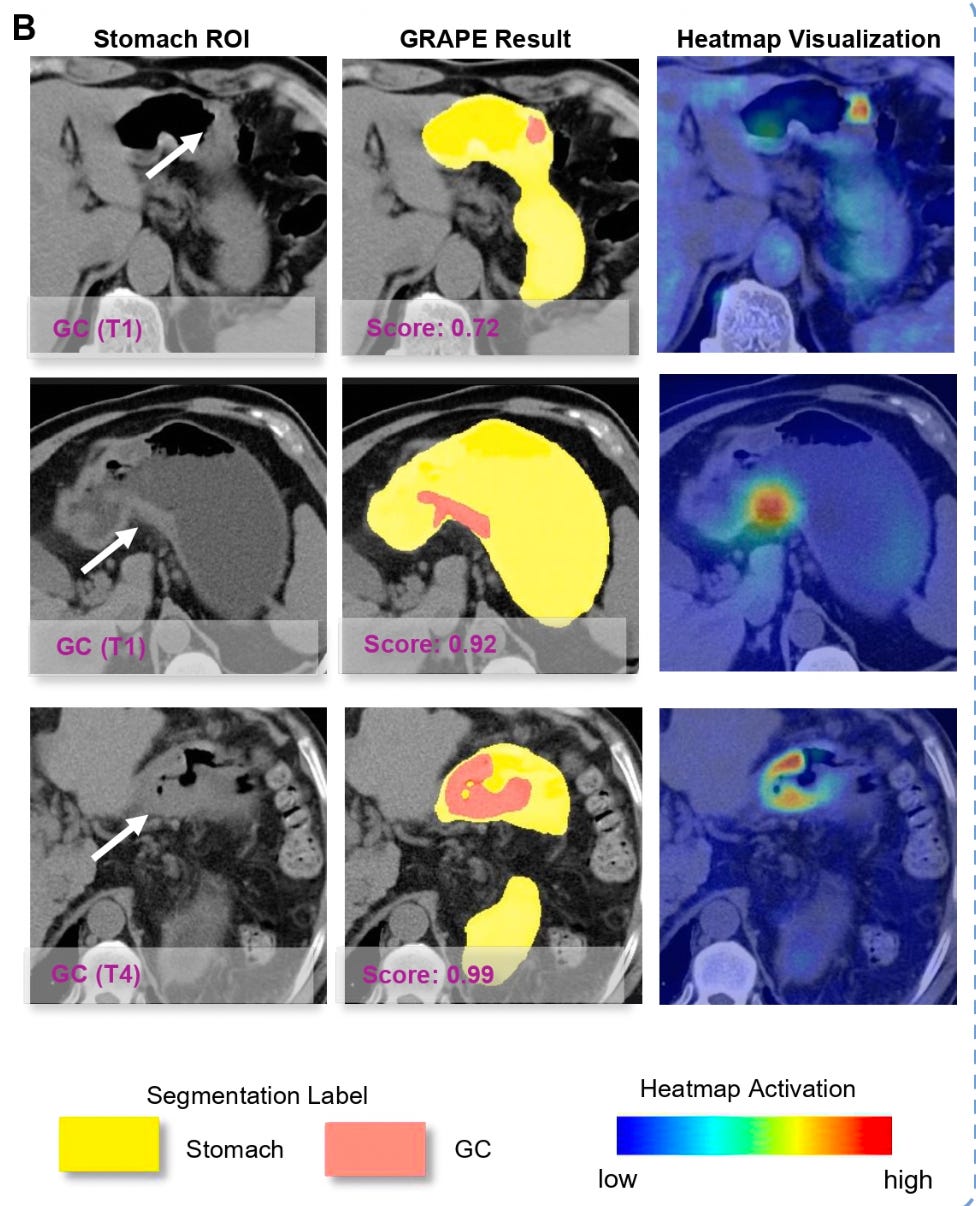

GRAPE model outputs: stomach region of interest, segmentation results, and heatmap visualization showing cancer detection across different stages (T1 and T4).

To put that in perspective: given China’s gastric cancer incidence of roughly 0.025%, if you randomly screened 10,000 people with gastroscopy, you might find 2 or 3 cases. But if you first ran them through the GRAPE model and only sent the “high-risk” group for gastroscopy, you’d find roughly 17 or more out of every 100 in that filtered cohort.